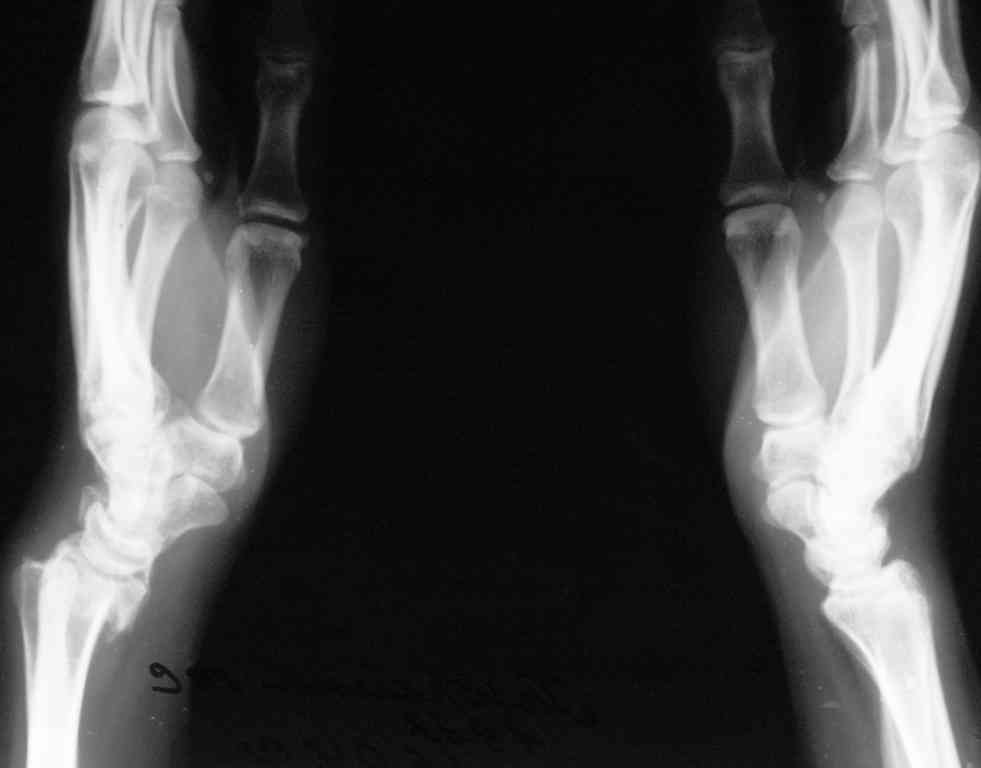

операцию А.М. Лаврукова упоминали на форуме, насколько я понял, она показана при псевдоартрозах ладьевидной кости с последующим формированием

артроза радио-ладьевидного сустава, в случае, который ты показал дегенеративные изменения очевидны и в радио-лунарном отделе сустава, следуя

логике, декомпрессия только одного отдела маловероятно улучшит функцию сустава в целом, мне так кажется. Отправлю тебе картинку с 6 летним результатом после проксимальной карпальной

резекции - для меня убедительно, может быть для тебя тоже будет интересна.